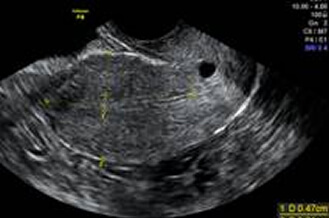

卵巣チョコレート嚢胞